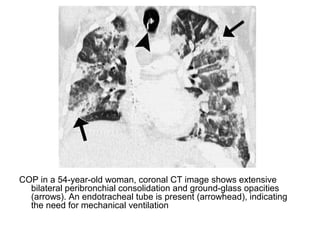

COP in a 54-year-old woman, coronal CT image shows extensive

bilateral peribronchial consolidation and ground-glass opacities

(arrows). An endotracheal tube is present (arrowhead), indicating

the need for mechanical ventilation